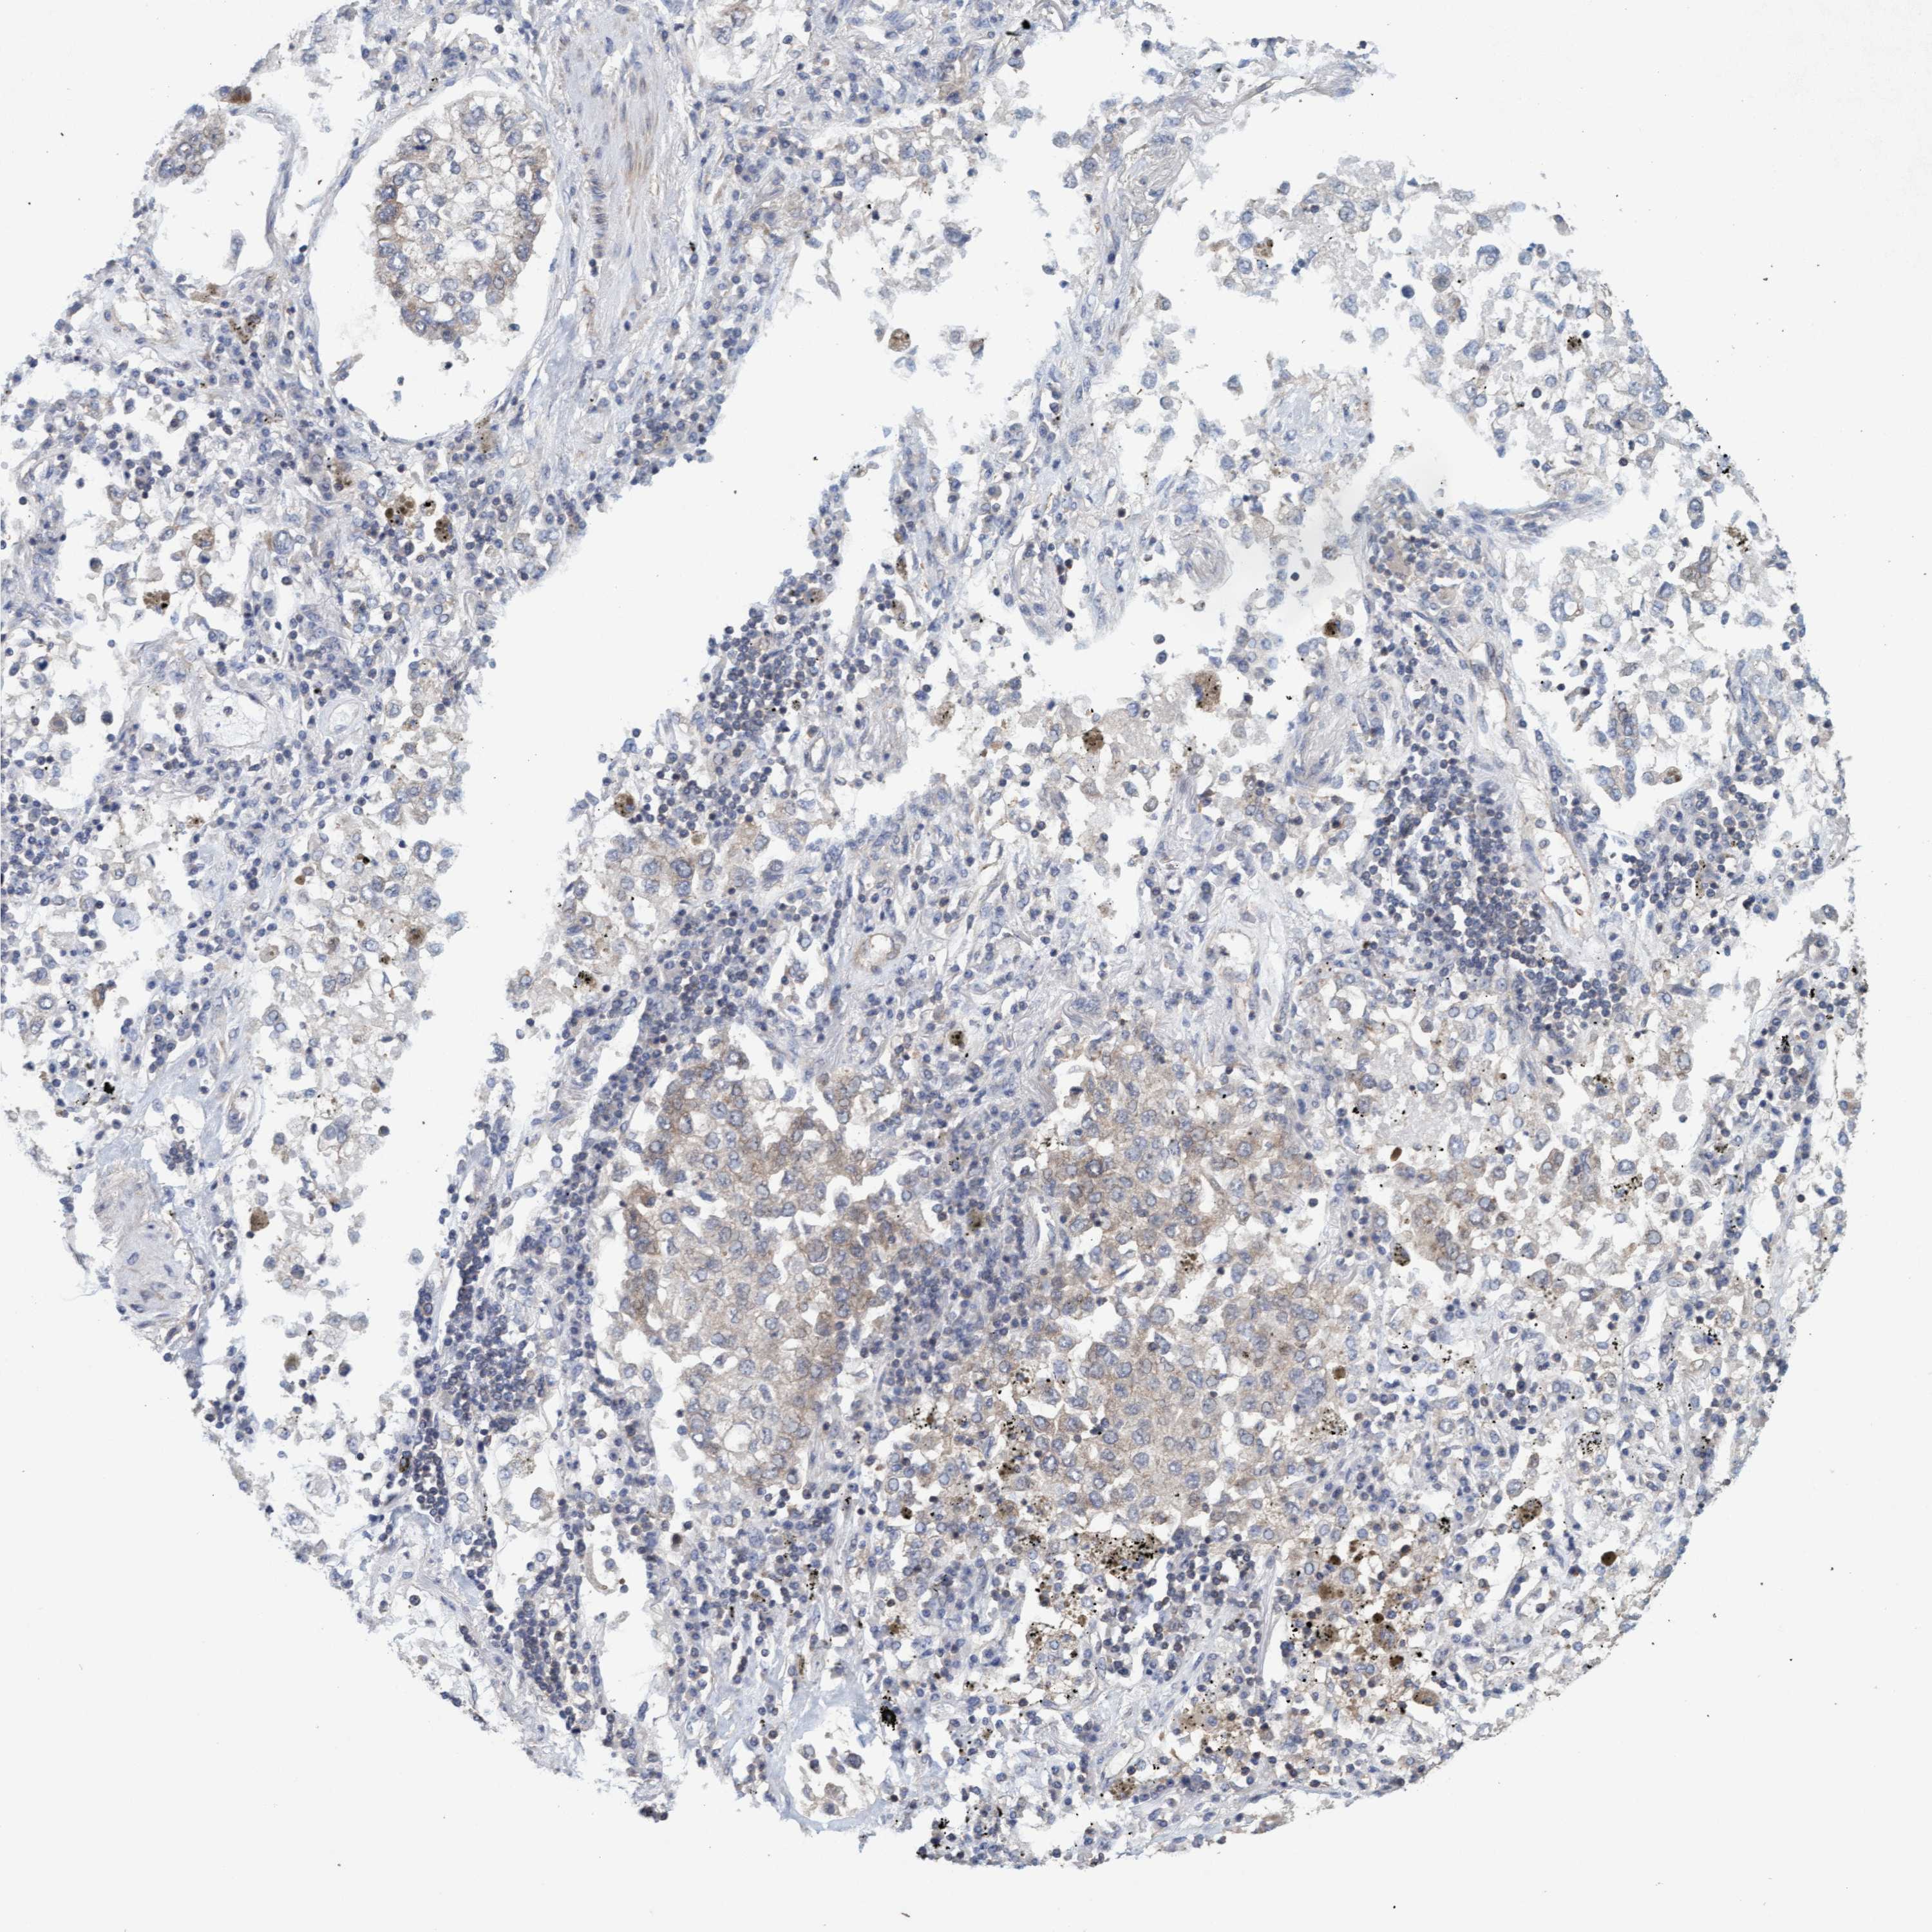

CANCER LUNG CANCER Show tissue menu

LUAD TCGA LUAD VALIDATION LUSC TCGA LUSC VALIDATION PROTEIN LUAD CPTAC PROTEIN LUSC CPTAC PROTEIN EXPRESSION

ANTIBODIES

AND

VALIDATION